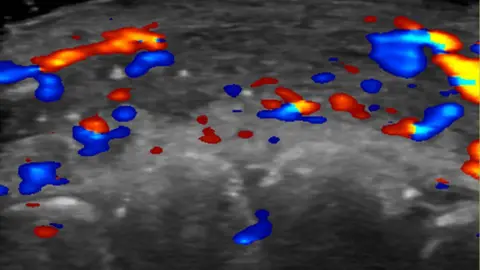

Researchers used ultrasound to study 100 cases of filler injections that had gone wrong.

In just under half the cases, ultrasound scans showed absent blood flow to small blood vessels that connect superficial arteries to deep ones in the face.

And in a third of cases, blood flow was absent in major blood vessels.

Rosa Maria Silveira Sigrist, M.D., and RSNA

Rosa Maria Silveira Sigrist, M.D., and RSNATo avoid complications in the first place, she advises clinics to use ultrasound to plan where to inject.

If complications do arise, ultrasound can guide where to treat.

“If injectors are not guided by ultrasound, they treat based on where the clinical findings are and inject blindly,” Dr. Sigrist says.

“But if we can see the ultrasound finding, we can target the exact place where the occlusion occurs.”

Rather than flooding the area with a drug called hyaluronidase to dissolve the filler, clinicians can do guided injections that use less hyaluronidase and provide better treatment results, she says.